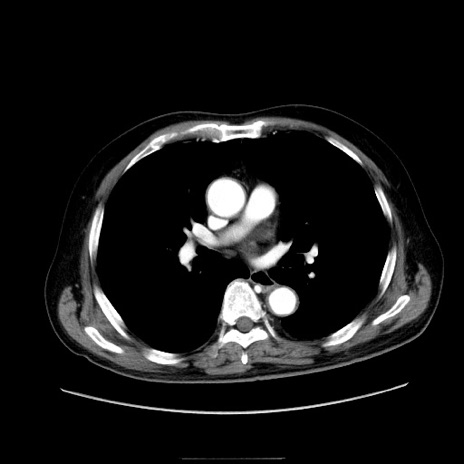

冠状断像

症例30(横断像)

【症例】80歳代男性

【現病歴】約6時間前から臍下部痛が出現。次第に腹部膨隆・背部痛も生じてきたため来院。背部痛の場所は変化しない。

【身体所見】意識清明、BT 36.3℃、BP  131/87mmHg、P 87bpm、SpO2 100%(RA)、臍周囲自発痛・圧痛あり、反跳痛なし、自発痛部位に一致して板状硬あり、腹部膨隆、腸雑音減弱、CVA tenderness両側陰性。